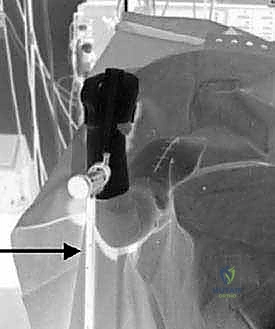

Computed Tomography (CT) scanning, preferably with advanced 3D reconstruction capabilities, is the current gold standard for quantifying glenoid version, assessing volumetric bone loss, and classifying the glenoid morphology according to the modified Walch classification system. Walch Type A represents a centered humeral head with concentric wear (A1 minor, A2 major central erosion). Type B denotes posterior subluxation (B1), posterior subluxation with biconcave posterior erosion (B2), or monoconcave posterior wear with severe retroversion (B3). Type C indicates profound glenoid hypoplasia with increased retroversion (>15 degrees) but without posterior subluxation. Type D represents anterior subluxation. Magnetic Resonance Imaging (MRI) is utilized selectively, primarily in patients with rheumatoid arthritis or those with clinical suspicion of a concomitant rotator cuff tear (e.g., profound weakness in external rotation or elevation), to confirm the structural integrity of the cuff prior to committing to an anatomic arthroplasty.

Digital Templating and Patient Positioning

The advent of sophisticated 3D digital templating software has revolutionized preoperative planning in shoulder arthroplasty. Surgeons can now import the patient's CT data to create a virtual 3D model of the scapula and humerus. This allows for precise measurement of glenoid version and inclination relative to the Friedman line (the axis from the medial border of the scapula to the center of the glenoid). Virtual implant placement enables the surgeon to determine the optimal size, configuration (pegged vs. keeled), and seating of the glenoid component. In cases of severe B2 or B3 glenoids, the software can simulate asymmetric anterior reaming to correct version, or template the use of augmented glenoid components (e.g., posterior step or wedge augments) to preserve subchondral bone while restoring the joint line.